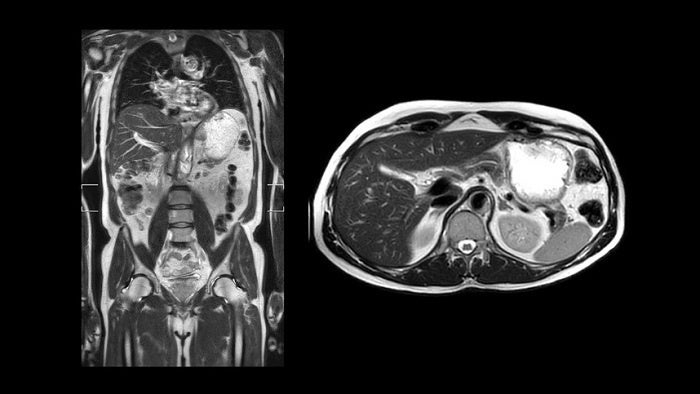

「MR 5300」は「Micro-coolingテクノロジー」により、高い静磁場安定性0.001ppm/hourならびに傾斜磁場直線性1.4%(50cmDSV時)を実現しており、最大FOV55cmにおいて歪みなく精度の高いMR検査を可能とします。

さらに本システムに新しく搭載された「Breeze coils(ブリーズコイルズ)」は、軽量性と柔軟性、コイル間の組み合わせの自由度に富んだコイルで検査部位への密着性に優れています(図2)。MR信号のデジタル変換をコイル内やコイル接続部で行うデジタルコイルであり、ノイズ混入を最小限に抑え画像のシグナルノイズ比(SNR)を最大限に引き出します。また、この「Breeze coils」は高速化技術Compressed SENSEの利用を可能にし、イメージクオリティーを損なうことなく最大50%の撮像時間の短縮[3]を図れます。また、撮像時間を延長せずに60%の空間分解能向上[3]を図ることもでき、限られた検査時間の中で確信度の高い画像診断を行うためのさまざまなニーズに対応できます。